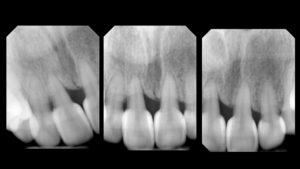

Final shaping was completed with the 3M® Soflex Coarse disc, followed by a final polish using Bioclear Magic Mix pre-polishing paste and the Bioclear Rockstar Polishing cup. (Figure 7) Rubber dam was removed, and the smile was evaluated for facial harmony. Adjustments were not needed for this patient as she was pleased with all aspects of her smile. (Figures 8-9) Post operative radiographs were taken to assess for excess composite and quality of technique and can be compared to the pre-operative x-rays. Post operative radiographs are useful for quality control. Notice how a smooth “infinity edge” can be created with the Bioclear matrices and technique. This is essential for a healthy tissue response. (Figures 10-11).

One of the greatest benefits of using Bioclear in closing black triangles is the added stability that periodontally weak teeth can obtain. In this case, stability was improved further at the two-year mark. (Figures 12-13) The 4-year results are proving to be color stable and free of inflammation (not shown). As often seen following cosmetic dentistry, the improvements are dramatic and result in a more relaxed and confident smile.